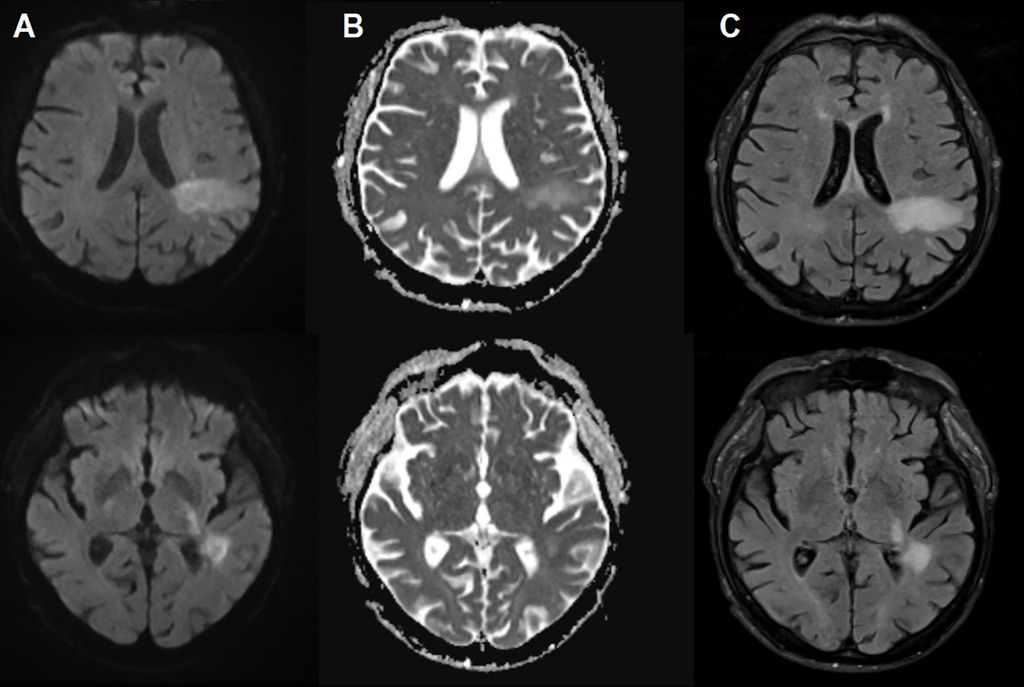

Biểu hiện của PML rất đa dạng và dễ nhầm lẫn với các bệnh lý thần kinh khác như đột quỵ hay đa xơ cứng. Người bệnh có thể gặp khó khăn trong việc nói, suy giảm thị lực, rối loạn vận động hoặc thậm chí co giật. Việc chẩn đoán thường dựa vào hình ảnh tổn thương đặc trưng trên não kết hợp với việc phát hiện DNA virus trong dịch não tủy.

Chỉ khi tiến hành chụp não, các bác sĩ mới phát hiện những tổn thương đặc trưng của PML. Xét nghiệm dịch não tủy sau đó xác nhận sự hiện diện của virus JC trong hệ thần kinh trung ương. Diễn biến bệnh diễn ra nhanh chóng và bệnh nhân đã tử vong chỉ hai ngày sau khi được chẩn đoán.